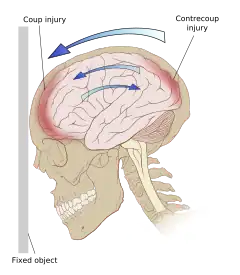

Even in the absence of an impact, significant acceleration or deceleration of the head can cause TBI; however in most cases, a combination of impact and acceleration is probably to blame.[37] Forces involving the head striking or being struck by something, termed contact or impact loading, are the cause of most focal injuries, and movement of the brain within the skull, termed noncontact or inertial loading, usually causes diffuse injuries.[20] The violent shaking of an infant that causes shaken baby syndrome commonly manifests as diffuse injury.[66] In impact loading, the force sends shock waves through the skull and brain, resulting in tissue damage.[37] Shock waves caused by penetrating injuries can also destroy tissue along the path of a projectile, compounding the damage caused by the missile itself.[23]

Damage may occur directly under the site of impact, or it may occur on the side opposite the impact (coup and contrecoup injury, respectively).[65] When a moving object impacts the stationary head, coup injuries are typical,[67] while contrecoup injuries are usually produced when the moving head strikes a stationary object.[68]